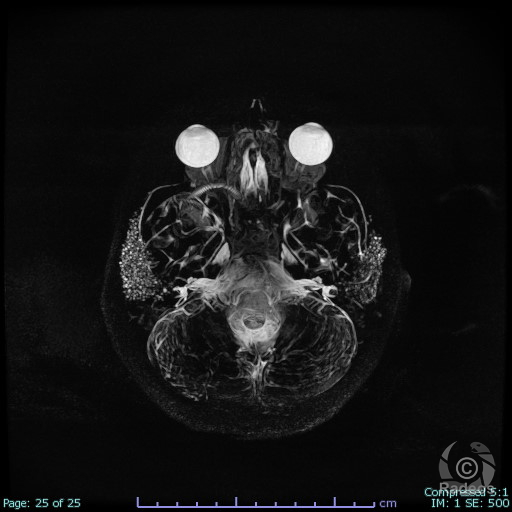

Aspect IRM d'une fibromatose profonde de la paroi abdominale. Découverte fortuite d'un angiome hépatique gauche.

Fibromatose profonde de type desmoïde